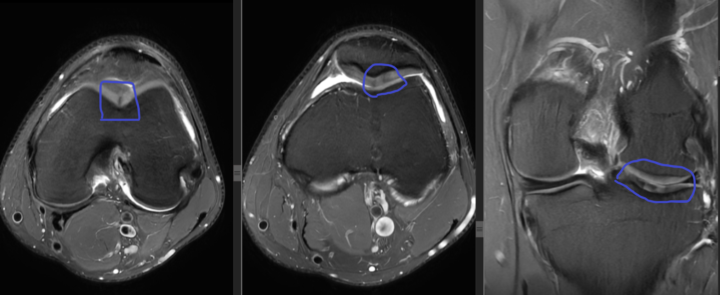

Knee chondral zones

Hi. Which classification do you use to specify the exact location of a cartilage defect in the knee joint?

0 likes • May 15

At my institution we use Outerbridge classification for chondral degeneration (grading from 1 to 4)